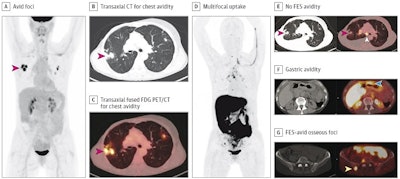

The patient was a woman in her 50s with suspected recurrence of invasive lobular breast cancer. A, maximum intensity projection image from FDG-PET/CT demonstrating avid foci in the chest (red arrow). Transaxial CT (B) and transaxial fused FDG-PET/CT image (C) showing that the chest avidity corresponds to FDG-avid lung nodules (red arrows) suspicious for malignancy. The lung nodule was subsequently biopsied but found to represent benign granulomatous inflammation and thus a false positive on FDG-PET/CT. D, maximum intensity projection image from FES-PET/CT demonstrating multifocal uptake suspicious for malignancy. E, transaxial CT and fused FES-PET/CT demonstrating no FES-avidity in the biopsy proven benign granulomatous lung nodules (red arrows), thus true negative on FES-PET/CT. FES-avidity in nodes (white arrow) is suspicious for malignancy. F, transaxial CT and fused FES-PET/CT demonstrates gastric avidity (blue arrow) suspicious for malignancy. G, transaxial CT and fused FES PET/CT demonstrates FES-avid osseous foci (yellow arrow) suspicious for malignancy. This osseous focus was subsequently biopsied and proved to be an osseous metastasis and thus true positive on FES-PET/CT.Image courtesy of JAMA Open Network